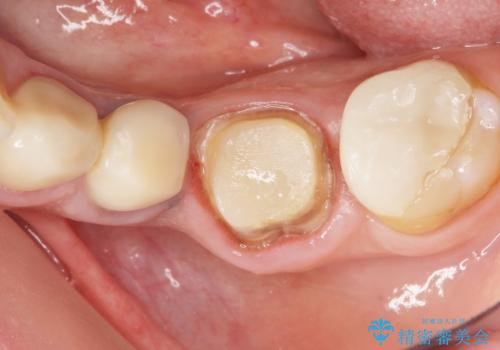

左下の奥歯(左下6)の劣化した白い被せ物と金属の土台を除去し、セラミッククラウンによる補綴治療を行いました。

- ¥286,000 (根管治療、土台、仮歯、クラウン) ※税込費用は治療当時の料金となります